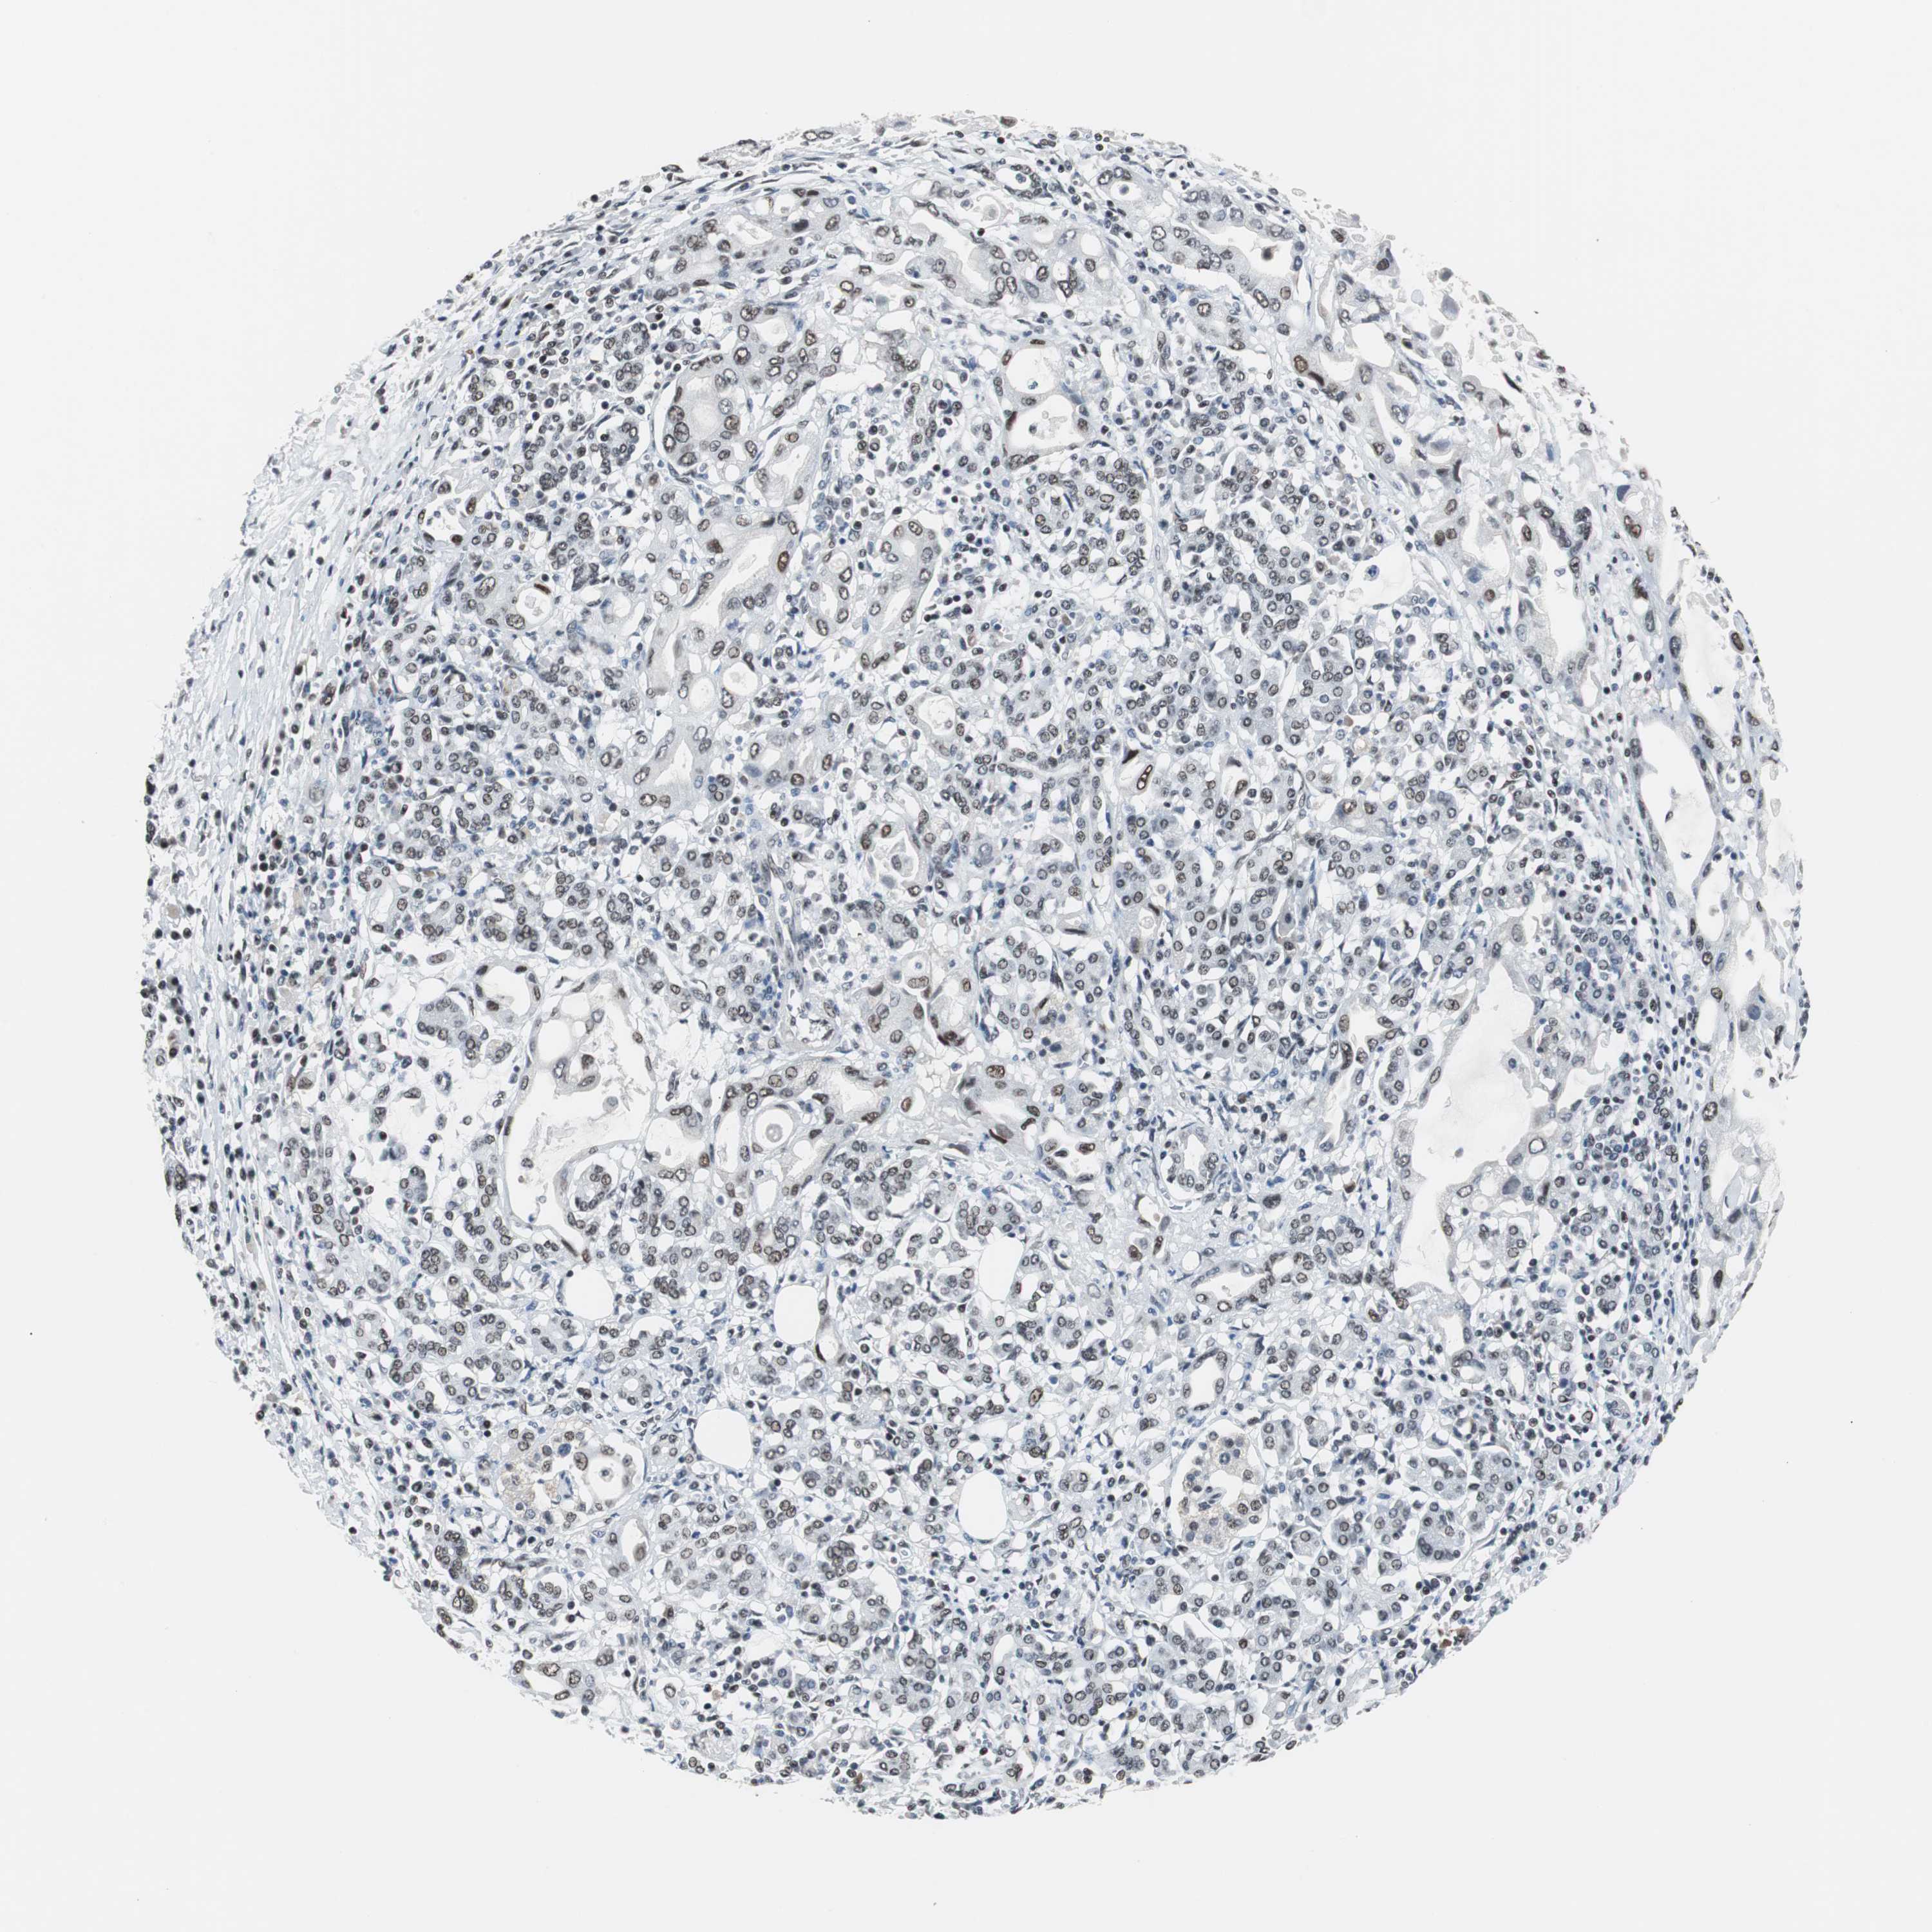

PANCREATIC CANCER - Protein expressioni

A mouse-over function shows sample information and annotation data. Click on an image to view it in a full screen mode. Samples can be filtered based on level of antibody staining by selecting one or several of the following categories: high, medium, low and not detected. The assay and annotation is described here.

Note that samples used for immunohistochemistry by the Human Protein Atlas do not correspond to samples in the TCGA dataset.

Antibody stainingi

Antibody staining in the annotated cell types in the current human tissue is reported as not detected, low, medium, or high, based on conventional immunohistochemistry profiling in selected tissues. This score is based on the combination of the staining intensity and fraction of stained cells.

Each image is clickable and will lead to virtual microscopy that enables deeper exploration of all samples and also displays staining intensity scores, fraction scores and subcellular localization as well as patient and tissue information for each sample.

Antibody HPA006429

Staining

High

Medium

Low

Not detected

Intensity

Strong

Moderate

Weak

Negative

Quantity

>75%

75%-25%

<25%

None

Location

Nuclear

Cytoplasmic/membranous

Cytoplasmic/membranous,nuclear

Adenocarcinoma, NOS

Adenocarcinoma, metastatic, NOS